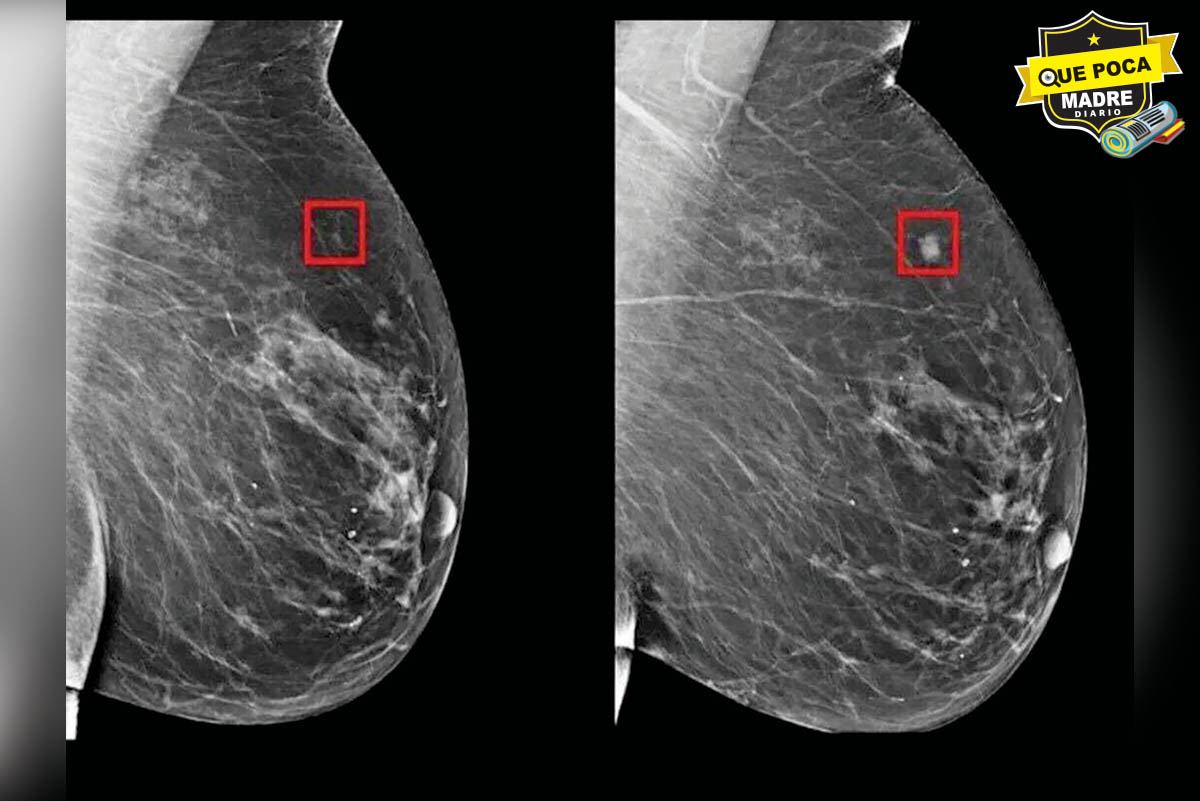

Con apoyo del Consejo Nacional de Humanidades, Ciencias y Tecnologías (Conahcyt), la doctora Marlet Themis inició con el proyecto científico que se enfoca en la búsqueda de las moléculas que puedan frenar la metástasis de las células cancerígenas, y así poder ofrecer a los pacientes otras alternativas médicas que puedan mejorar o terminar con la enfermedad.

Los estudios de acoplamiento molecular arrojaron que los fármacos que intervienen en la metástasis y tiene mayor potencial para inhibir la unión de las moléculas con la loperamida (usado para enfermedades diarreicas) y la glipizida (medicamento para la diabetes tipo 2).